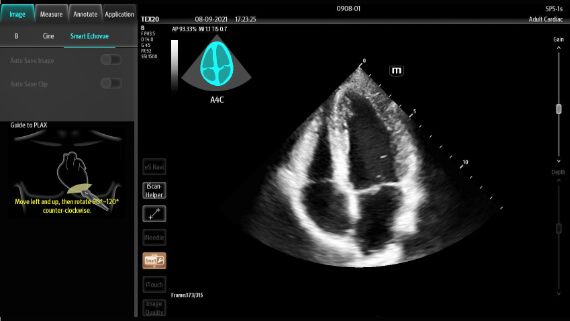

Point of Care, Reimagined

The TEX20 Series ultrasound system helps clinicians reimagine their clinical practice in demanding point-of-care environments like critical care, emergency medicine, and anaesthesia.

X-Pilot: Clinical Application-Oriented Workflow

Based on the professional society guidelines for point of care ultrasound, the X-Pilot suite integrates historical diagnostic images and multi-organ data into a concise and precise view of the patient status to support rapid clinical decisions at the bedside.